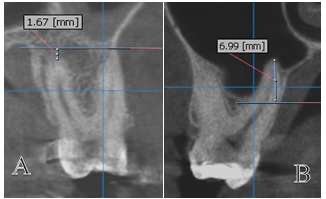

拔牙後3-4個月大多數患者均已完成癒合,但仍有極少數案例仍未達100%癒合的情況,本人以自身經驗以下圖進行解說(為極少數案例特別紀錄):

絕大部分患者在拔牙3-4個月後均已經是骨癒合情形,因爲是常見情況,故本人不會進行記錄。(我只會記錄罕見情況。)

以下圖為例,一般拔完牙後均等待數個月牙肉及齒槽骨癒合後,再進行植牙評估與植牙、補骨手術。(除非是少數齒槽骨條件極差的情況,需重建後才能植牙!)